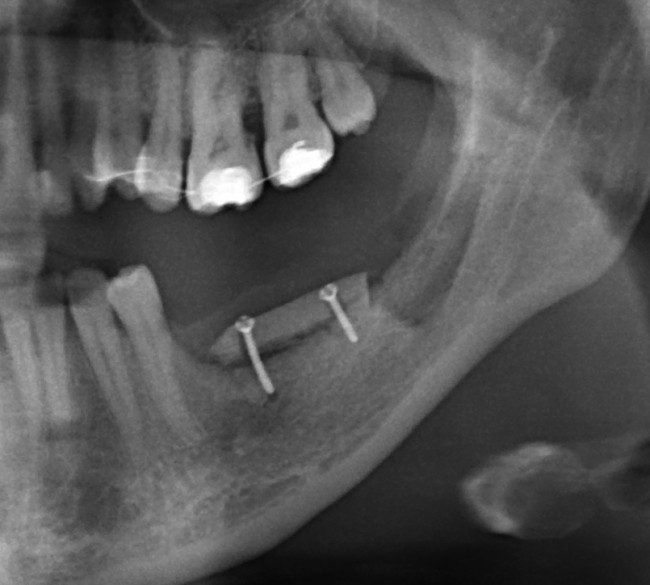

Снимок после проведенной имплантации:

после имплантации 2

Винты, фиксировавшие блок, удалены. Имплантаты позиционированы по разметке ортопеда, исходя из планируемой ортопедической конструкции.

Многих пациентов также интересует, как заживает тот участок челюсти, с которого был взят костный блок для пересадки. На снимке выше очень хорошо видно, что через три месяца костная ткань там почти полностью восстановилась — область забора блока еле видна.

Вот схема:

Sketch1051936

На верхней челюсти — микровинты в качестве кортикальной опоры, необходимой для интрузии зубов. Поскольку костная ткань верхней челюсти не очень плотная, и винты, как оказалось, не дают нужной поддержки, в дальнейшем планируем заменить их на микропластину.